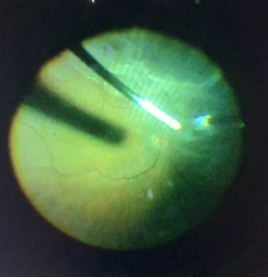

玻璃体视网膜手术

在最能体现眼科实力和高技术水平的微创眼底病手术方面,我们也呈现高速发展的态势。我科于2009年已开展眼底手术,能够开展复发性视网膜脱离、复杂性眼外伤、增殖性糖尿病视网膜病变、高度近视黄斑裂孔、儿童青少年视网膜脱离等几乎所有疑难玻璃体视网膜疾病的手术,广泛得到眼科同行的认可。目前科室影响力已覆盖周边8个省,不少疑难眼底疾病的患者经同行介绍至我院眼科进行进一步诊治。